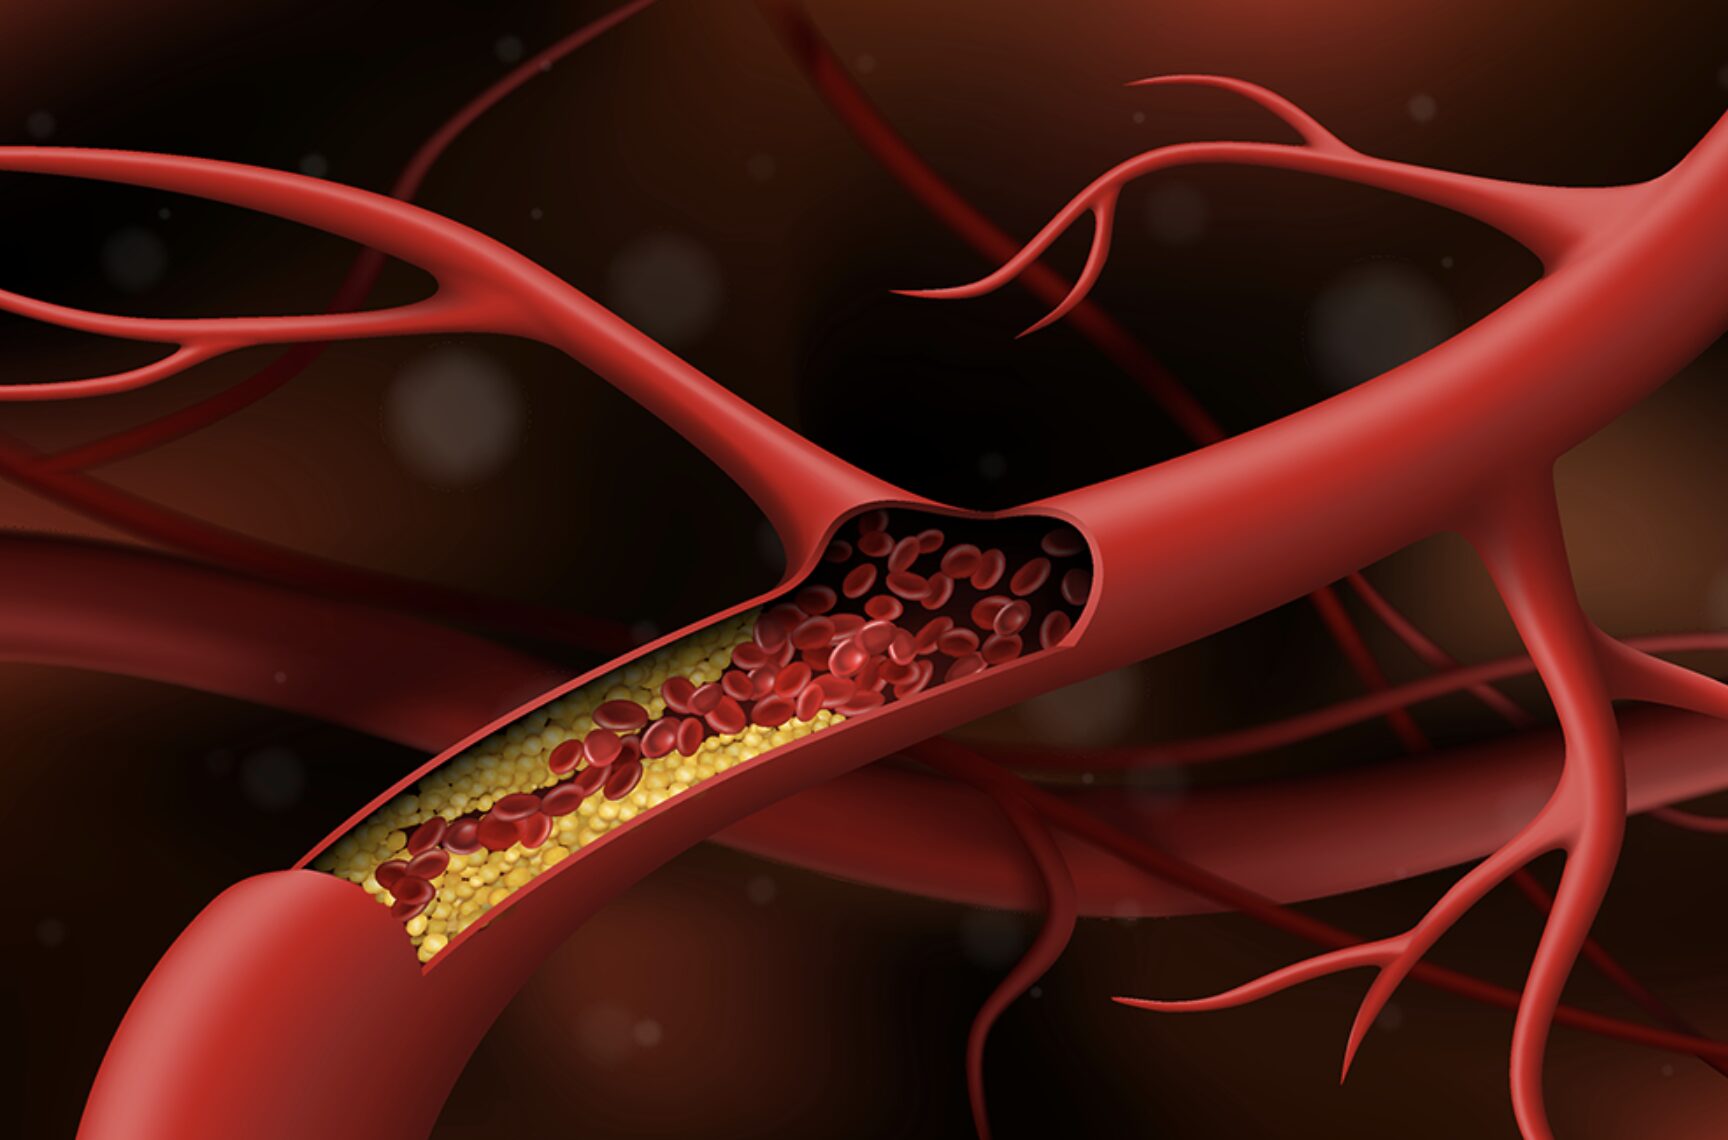

Đột quỵ do tác hại của hút thuốc lá

Thuốc lá là chất chứa nhiều độc tố đối với cơ thể con người như nicotin, hắc ín, formaldehyde, cyanid… hút thuốc lá làm tăng nguy cơ vữa xơ động mạch, gây đột quỵ, đồng thời, mắc những bệnh lý tim mạch, răng miệng và cả bệnh ung thư.

Cơ tim giãn hình thành cục máu đông gây đột quỵ nhồi máu não

Cơ tim giãn là căn bệnh nặng, có tiên lượng xấu và có tỷ lệ tử vong khá cao. Bệnh lý này nếu không được phát hiện và điều trị kịp thời sẽ gây các bệnh nghiêm trọng về tim mạch như: Hở van tim, suy tim, rối loạn tâm trương,… Thậm chí, có thể dẫn đến đột quỵ hoặc tử vong.